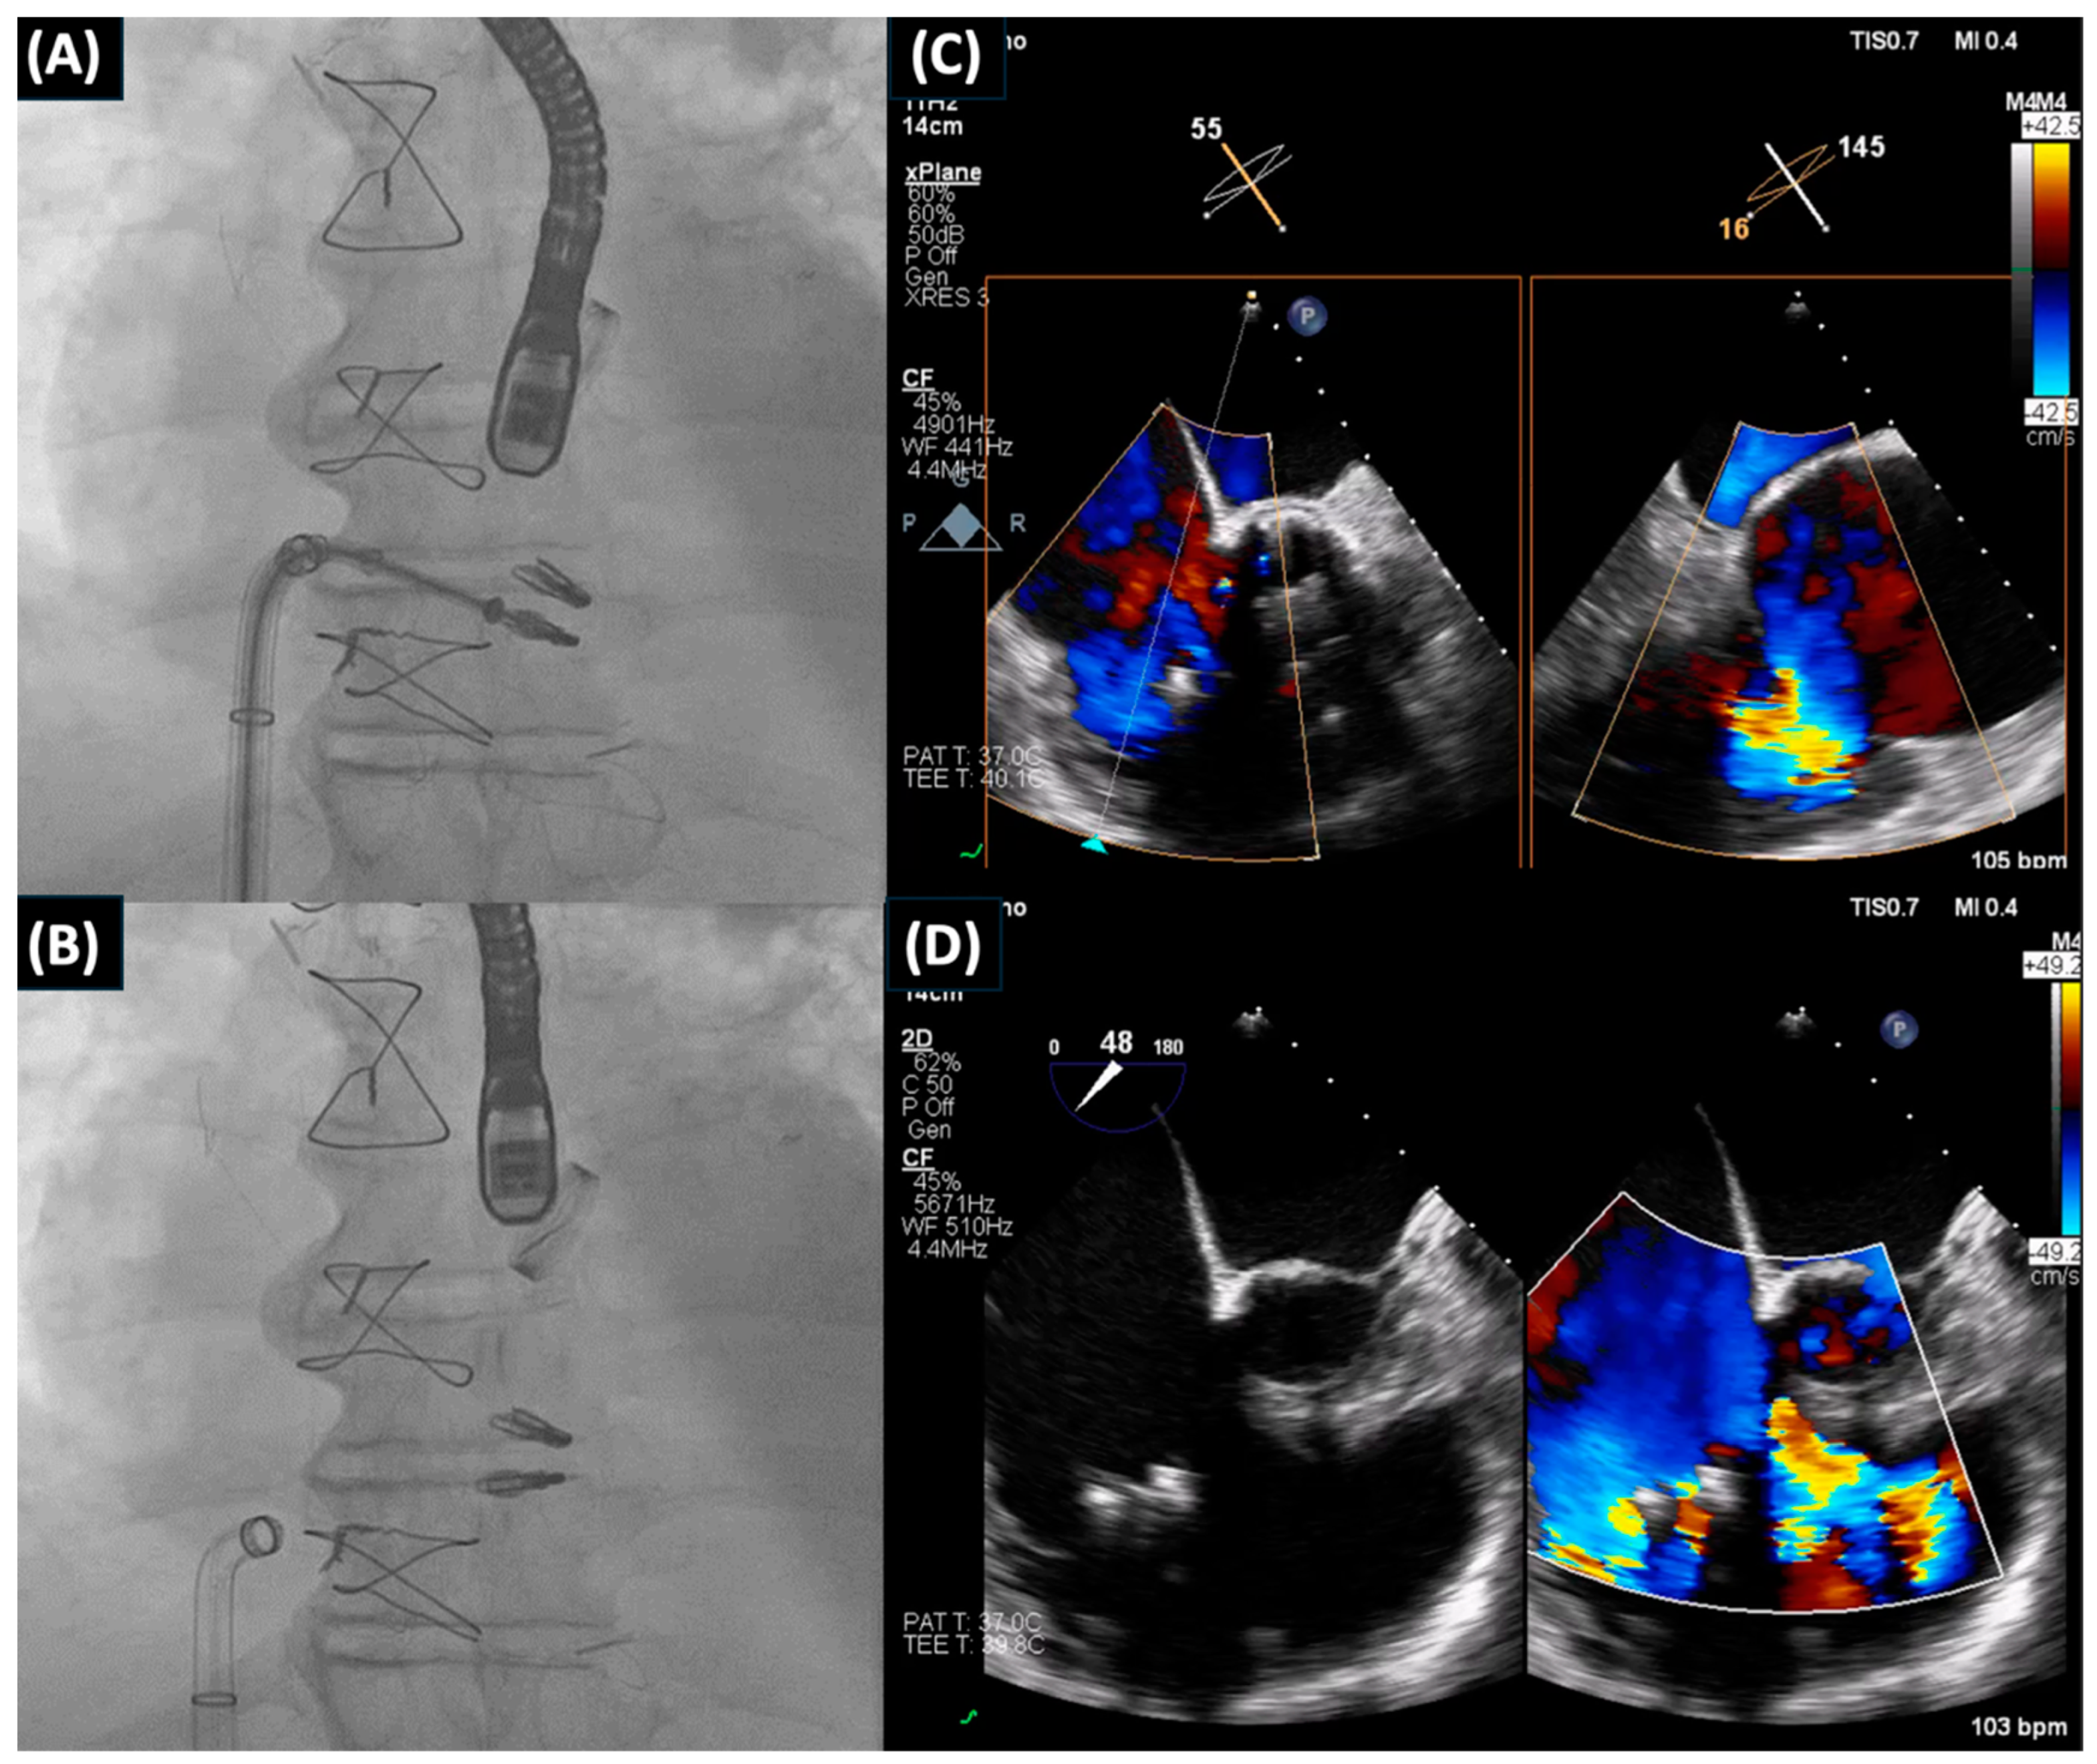

- Scotti, A.; Curio, J.; Leone, P.P.; Ludwig, S.; Coisne, A.; Sturla, M.; Murthy, S.; Chau, M.; Granada, J.F.; Jorde, U.P.; et al. Management of Volume Overload in Severe Atrial-Functional Tricuspid Regurgitation: Improved Feasibility of Transcatheter Edge-to-Edge Repair. JACC Case Rep. 2023, 12, 101776. [Google Scholar] [CrossRef] [PubMed]